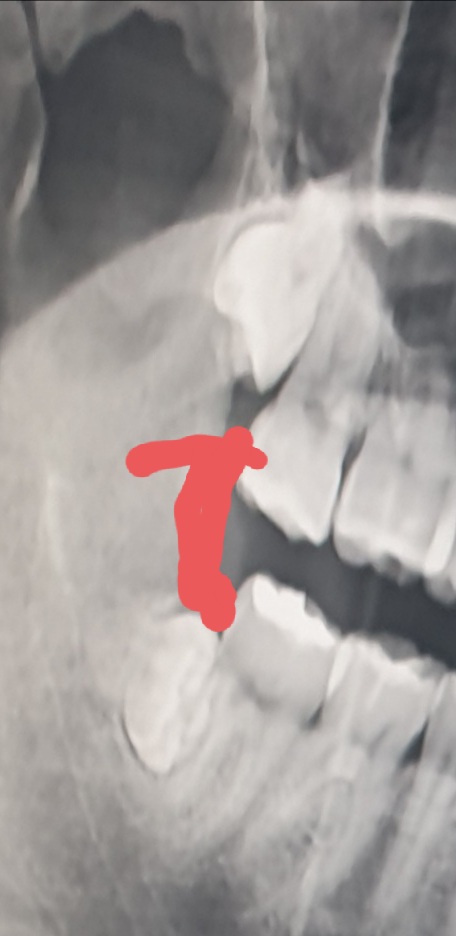

[일반] 사랑니 7일차 아직아파뒤짐

밑에거는 생각보다 안아픔

빨간선이 잇몸살인데

위에게 진짜 너무깊어서그런지 통증이시발 미칠거같네 드릅게아픔

위에꺼는 빼는것도 일이겠다;;

위에거 안빠져서 의사샘이 낑낑대다가 망치로때림

와 윗사랑니 저렇게 박힌건 또 첨보네

맨날 곧게나서 노출된 것만 봤는데 ㄹㅇ 아플만 하겠다ㄷㄷ

오우...오지게 박혀있네

위에껀 존나 깊어서 신경 존나 붙어있었나보네

위꺼 매복이 무슨 존나 깊네ㅋㅋㅋ